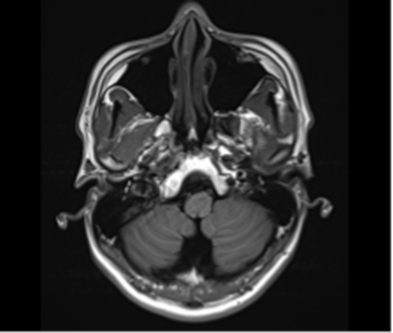

MRI 결과를 확인하는 순간 정말 안도했습니다.

다행히 뇌에는 이상 소견이 없었거든요.

그림11.png 촬영 일시: 2025.04.29

<Fig 1. 정상 뇌 MRI>

하지만 여전히 안면신경 자체의 문제는 남아있는 상태였어요.

환자분께 결과를 설명드렸습니다.

뇌에는 다행히 이상이 없어요

하지만 안면신경에 염증이 생긴 것 같으니

지금부터 집중적으로 신경 치료를 해보겠습니다